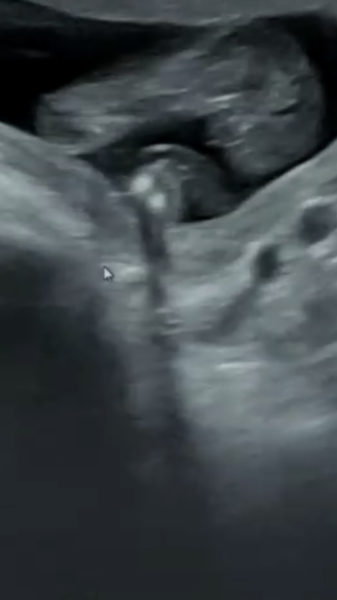

Told wrong gender at ultrasound??

Has anyone ever been told boy and it turned out to be a girl? Or the other way around?

My 16 week ultrasound at window to the womb looks like a girl in some images but I was told boy. I know they are probably correct but feel like I can’t buy anything yet as it doesn’t look very ‘boyish’.

It was a private gender scan. I’ve been googling boy gender 16 weeks scans and these look nothing like a boy to me? Confused Not long until my 20 week scan but wanted to be able to at least look at clothing for either gender online (I don’t want all white or yellow clothing).

The 3rd pic deffo looks like a boy to me. I could deffo tell my boys were boys when I had my scan I seen it before the sonographer.

I'm not a sonographer but that really does look like a boy to me.

They look like the scans I had 🤷🏻‍♀️, 2 boys.